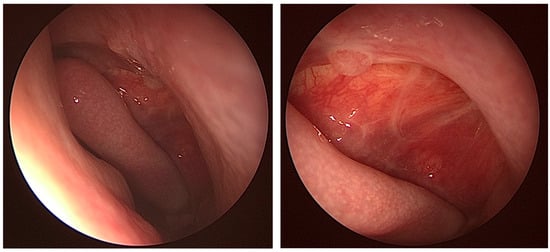

Fungal Sinusitis Masquerading as Trigeminal Neuralgia in an Immunocompetent Patient: A Case Report

Previous cases of trigeminal neuralgia (TN) caused by fungal sinusitis have been reported, but mainly in immunocompromised patients. We present a case of fungal sinusitis masquerading as trigeminal neuralgia in an immunocompetent patient and discuss the potential implications of these two diseases. The patient is a 59-year-old male who presented with a four-year duration of left facial pain. He had been diagnosed and treated for trigeminal neuralgia by a pain specialist but was subsequently referred to ENT after a MRI of the brain showed left maxillary sinusitis. Nasoendoscopy findings and a CT scan of the paranasal sinuses were concordant with left maxillary sinusitis. The patient underwent left functional endoscopic sinus surgery and recovered uneventfully. Our study shows that even in immunocompetent patients who present with non-resolving or worsening facial pain resembling the original diagnosis of TN, clinicians should remain vigilant for the possibility of alternative underlying pathologies including fungal sinusitis. Full article